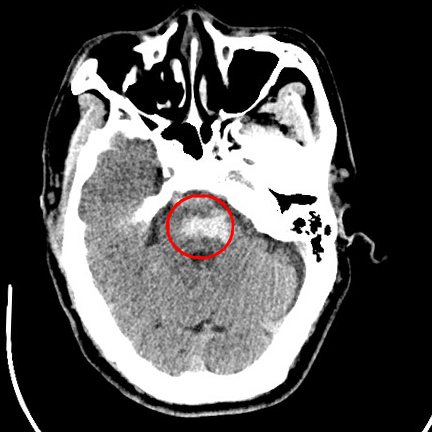

2月初,因在家中突发昏迷,王大爷被家人送来我院。医生诊断其为“脑干出血”,紧急收住EICU,期间出现房颤、肺栓塞等棘手并发症。

【脑干出血CT图】

“患者出血位置位于脑干,容易出现运动功能障碍。”高潮说,患者能如此迅速恢复行走站立功能让医护人员惊喜,也证实了重症患者早期康复介入的必要性。